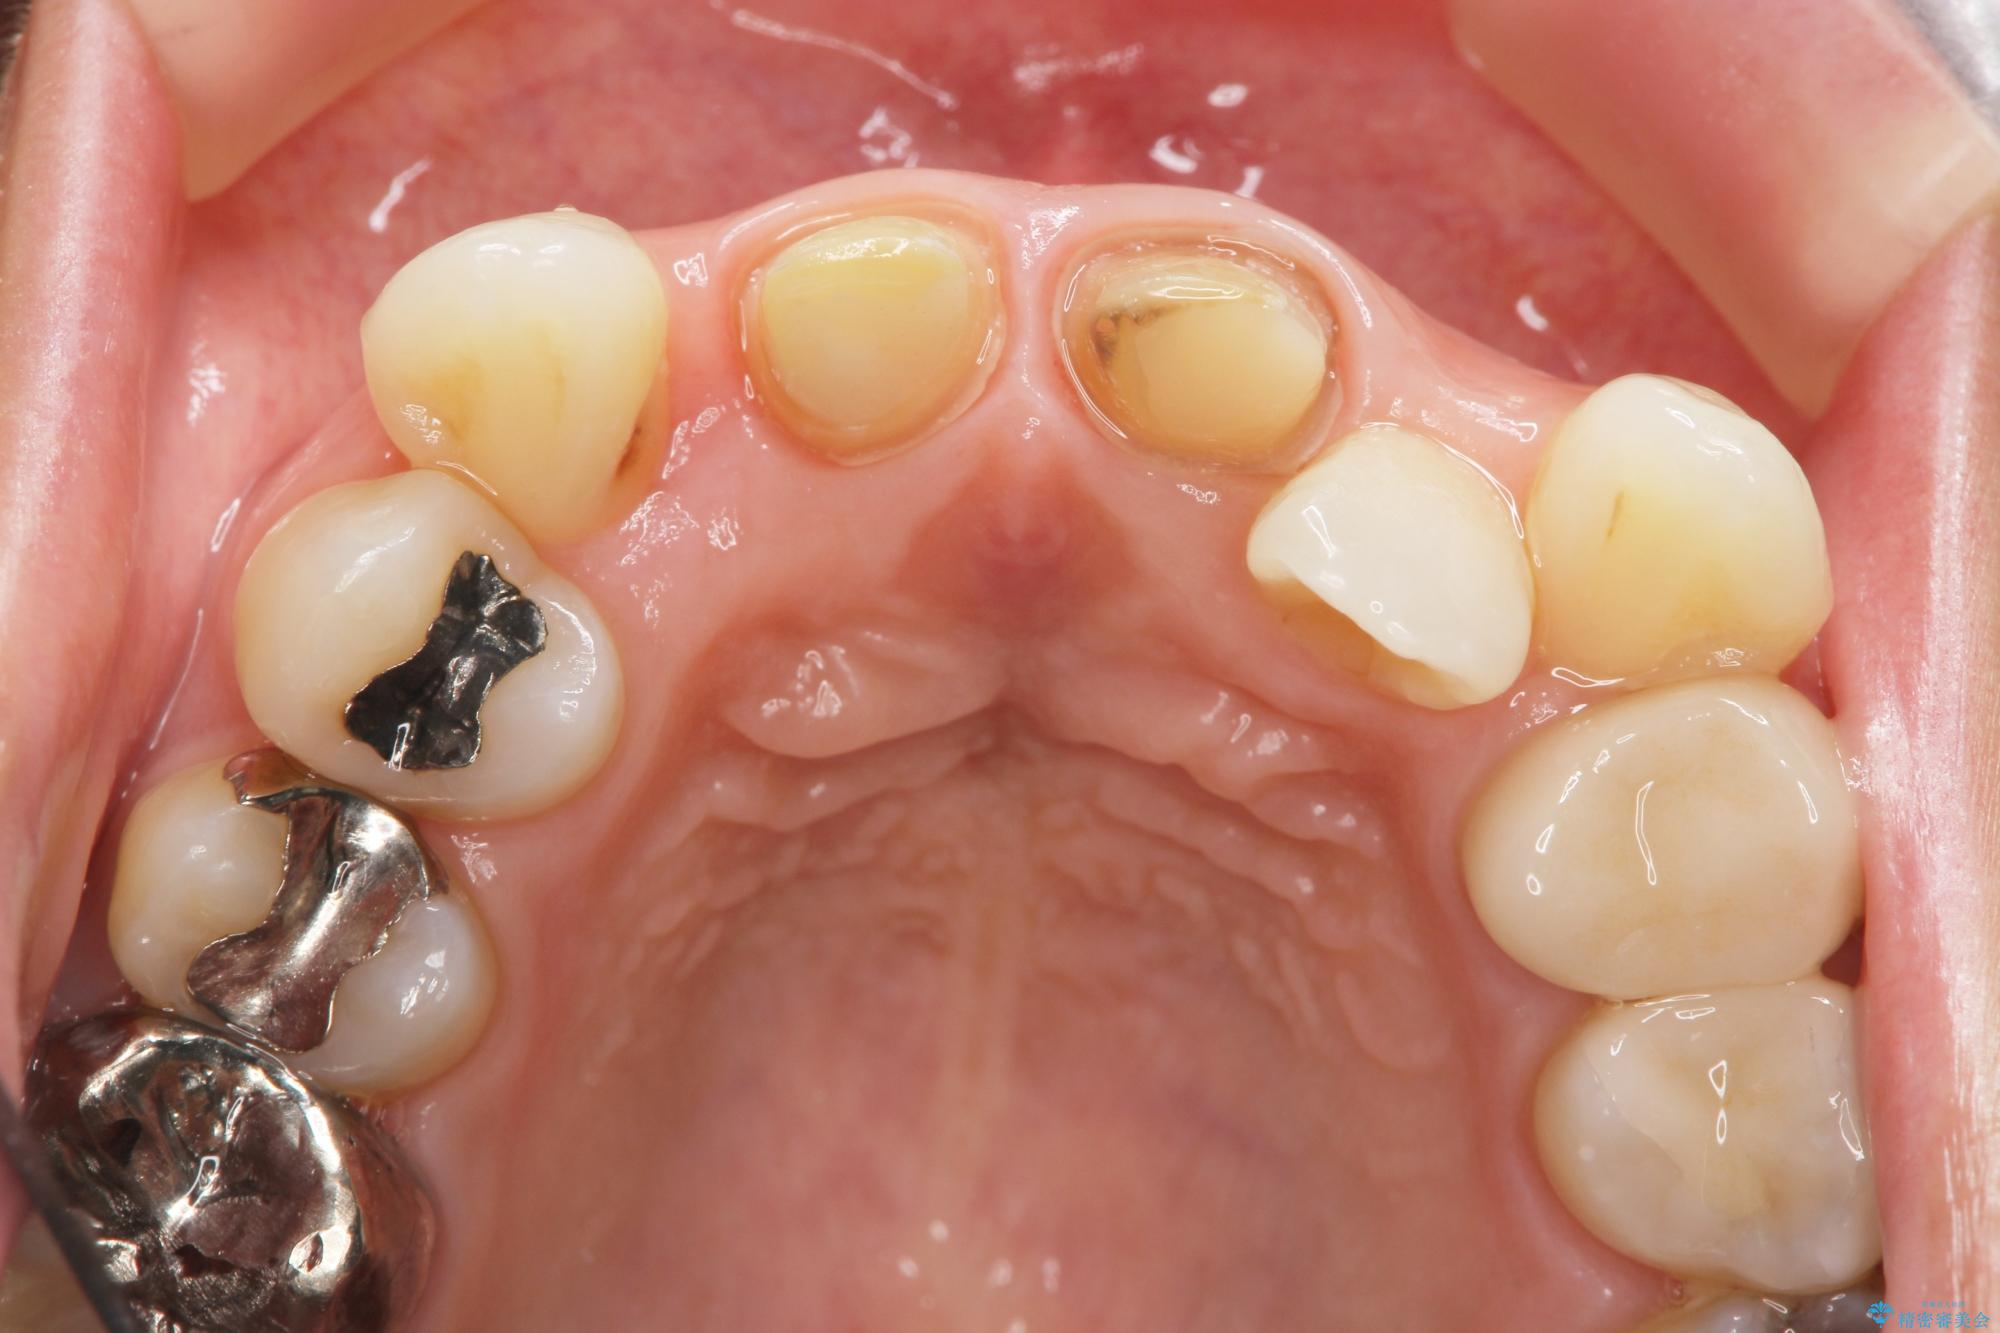

前歯の変色が気になるとご来院された患者様です。

レントゲン検査の結果、以前の根管治療の詰め物が突き出た状態でしたので、まず精密な再治療を行います。同時に、歯磨きがしにくく虫歯の原因になっている右上側切歯を抜歯し、その後、セラミック治療で全体を美しく修復する計画です。